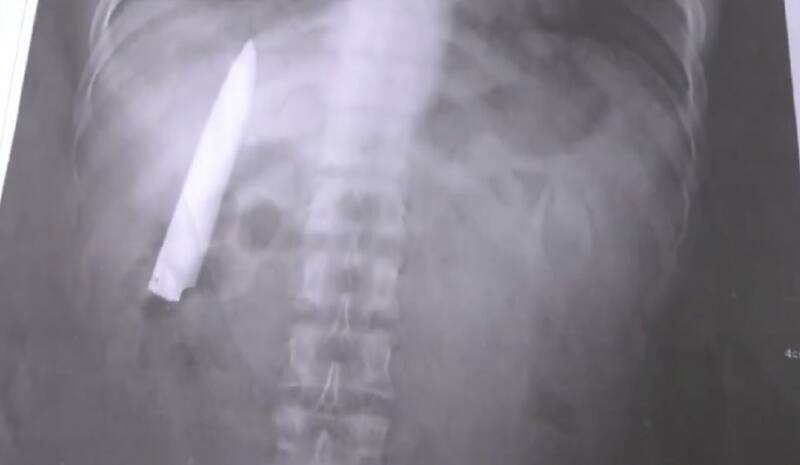

Una extraña suerte es la que vivió el filipino Kent Ryan Tomao, de 25 años, quien en enero del año pasado fue asaltado por un grupo de delincuentes, quienes lo apuñalaron en el tórax, pero por fortuna sobrevivió para contarlo. 14 meses después de ocurrido ese hecho, y mientras se realizaba unos exámenes médicos, le descubrieron que la hoja del puñal seguía en su cuerpo como si nada.

Pero su suerte volvió a sonreírle de una forma muy curiosa, ya que hace unos días comenzó a postular a un trabajo, donde le pidieron exámenes médicos, entre ellos radiografías de cuerpo completo. Fue ahí que le descubrieron la insólita negligencia. "Cuando llegué herido en aquella oportunidad, el médico que me atendió solo me suturó, sin pensar que adentro aún estaba la hoja del cuchillo", contó el afectado.